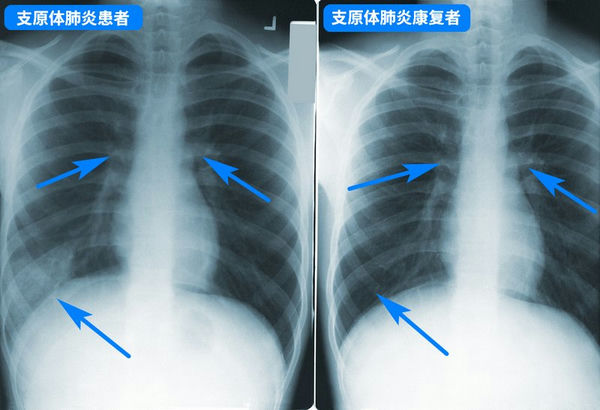

支原體肺炎胸透片

支原體肺炎***般并不嚴重,但要小心預防病情加重,盡早就醫(yī),如持續(xù)發(fā)燒5天以上、劇烈咳嗽不止,則***定要就醫(yī),以評估肺部是否受影響,以及是否存在并發(fā)癥。兒童支原體肺炎***般用阿奇霉素等大環(huán)內酯類藥物,但因為亞洲地區(qū)濫用藥物引起的耐藥性問題,很可能效果不佳,需要中途換藥,具體應該遵醫(yī)囑。